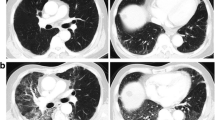

The presence, extent and distribution of the CT criteria for ILD were determined on the basis of a previous study [18, 19]; pre-thoracic RT CT findings were reviewed by two chest radiologists as no evidence of ILD (score 0), slight ILD (score 1), mild ILD (score 2) or moderate ILD (score 3) (Fig. 1). Slight ILD was defined as focal or unilateral ground-glass attenuation, focal or unilateral reticulation and patchy ground-glass abnormalities (<5 % of the lung). Mild ILD was defined as follows: non-dependent ground-glass abnormality affecting more than 5 % of any lung zone, non-dependent reticular abnormality, diffuse centrilobular nodularity with ground-glass abnormality, honeycombing, traction bronchiectasis, non-emphysematous cysts and architectural distortion. Moderate ILD was defined as bilateral fibrosis in multiple lobes associated with honeycombing and traction bronchiectasis with a sub-pleural distribution.

Typical CT images used to determine the ILD score. Score 1 predominant peripheral reticular abnormalities with a small amount of ground-glass opacity without honeycombing (a). Score 2 predominant peripheral reticular abnormalities with both ground glass opacity and a small amount of honeycombing (b). Score 3 predominant peripheral and basal reticular abnormalities. Including traction bronchiectasis, the CT findings of a score of 3 are more remarkable than those of a score of 2 (c)

The median follow-up period was 11.8 months for all patients. Subclinical ILD was recognized in 11 (18 %) of the 62 patients. A total of 51 patients had no evidence of ILD (score 0),while there were no patients with slight ILD (score 1), three patients with mild ILD (score 2) and eight patients with moderate ILD (score 3).

Grade 2–5 RP was recognized in eight (13 %) of the 62 patients: Grade 5 in three patients and Grade 2 in five patients. RP occurred between 1.8 and 6.4 months (median 4.7 month) after the start of thoracic RT. Table 2 shows the relationships between the clinical factors and Grade 2–5 RP in all patients. Subclinical ILD was a significant factor predicting the occurrence of Grade 2–5 RP (p = 0.0274). Grade 2–5 RP was observed in four (36 %) of the 11 patients with subclinical ILD. Subclinical ILD tended to be a significant factor associated with the occurrence of Grade 5 RP (p = 0.0785); two patients with subclinical ILD, one patient without ILD and two of the three patients with Grade 5 RP had an ILD score of 3 (Table 3; Fig. 2). All of the patients with Grade 5 RP exhibited extensive RP beyond the irradiated field, including the contralateral lung. Analyses of the correlation between the ILD score on CT and the RP grade using Spearman’s correlation coefficient showed these parameters to be significantly related (Table 4; r = 0.253, p = 0.048).

A case with Grade 5 RP (case 1 in Table 4). a, b CT images prior to thoracic RT. A score of 3 for subclinical ILD was recognized. c CT with dose distribution. Red, light blue, yellow, green and blue lines are 50.4, 45.4, 25.2, 15.1 and 2.0 Gy, respectively. d A CT image taken 1.8 months after the completion of thoracic RT showed extensive ground-glass abnormalities and focal consolidations